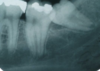

What radiographic sign is this showing in regards to M3M surgery risk to ID canal

Diversion / deflection of ID canal